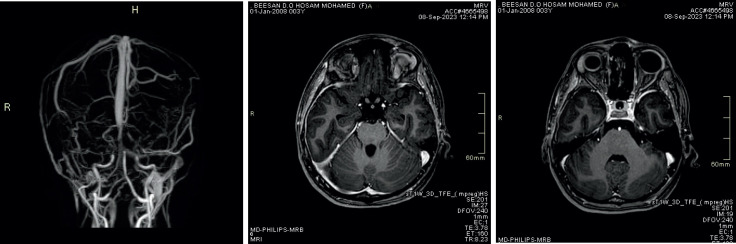

Post -contrast Three -dimensional MP RAGE T1WI Sequence Compared to Brain MRV Sequence for Diagnosing Brain Sinus Venous Thrombosis.

Background: Dural sinus thrombosis is considered as a one of the clinical and radiological emergencies that require special attention and high index of suspicion and needs combined effort of both the treating physician and the radiologist to obtain proper diagnosis and subsequently proper management.

Objective: The aim of this article was to compare the accuracy of MRV TOF and post contrast MP-RAGE sequences in diagnosis of cerebral sinus venous thrombosis.

Methods: After all informed consents were obtained and upon ethical committee approval from the ethical committee in Joradanian Royal medical services in Amman we perform this study as a retrospective study done on 50 patients with cerebral sinus venous thrombosis with 50 pateints control group done at king Hussein medical center in Amman Jordan.

Results: The guidelines and regulations of studies conducted in Royal medical services were followed. 68 females and 32 males with age range between 19 and 52 years. All patients underwent brain MRI for evaluation of cerebral sinus thrombosis, all studies were done on seimens skyra 3 Tesla machine with standardized protocol including 2 D TOF MRV, axial T2WI, axial FLAIR, Axial T1, SWI and diffusion weighted images along with 3D MP-RAGE post contrast. Images were reviewed by two well experienced neuroradiologists (Maysoon and Qamar) in separate sessions, each MRI sequence was reported separately without knowing patients name or clinical history. Conclusion: The results for T2 WI, SWI, MRV TOF and MP-RAGE post contrast were reported. We used a confidence level score to standardize the results. Then the results were analyzed using simple statistical methods.